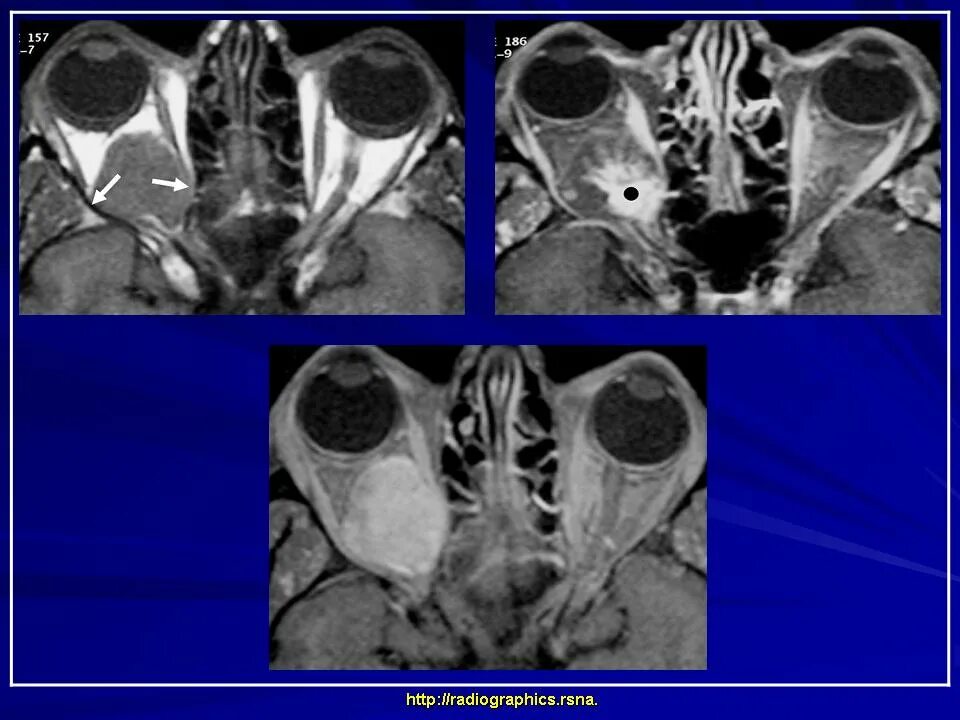

Данные кт